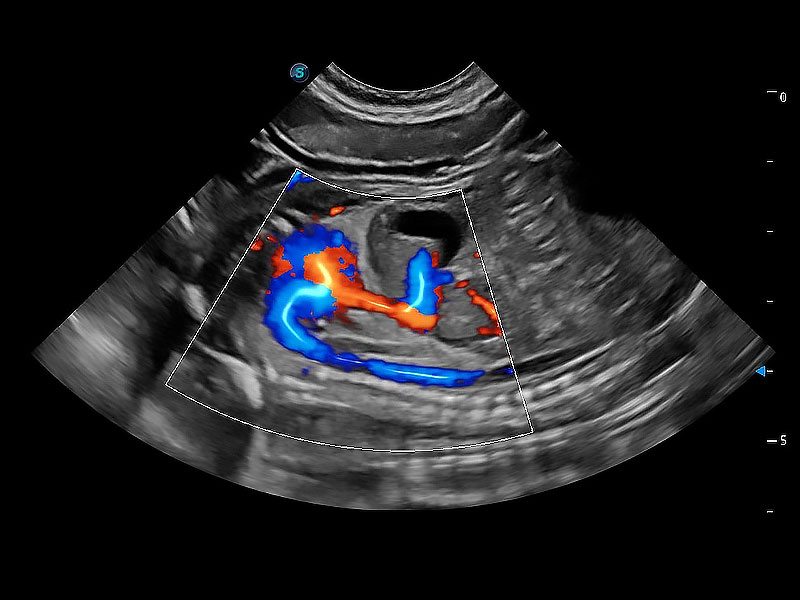

• Bright Flow 立体血流成像

在传统二维血流成像的基础上,呈现血流的立体感,具有动感的生命力之美。即便是微小的血管也能轻松应对,提高了血流的视觉敏感性。

(犬)胎儿主动脉弓立体血流